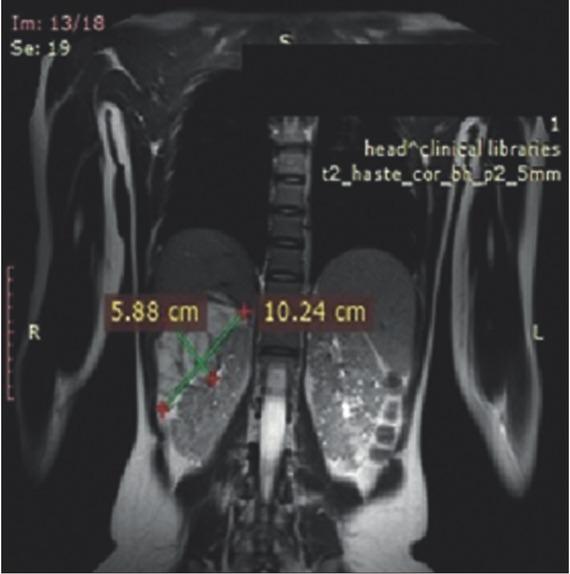

Magnetic resonance imaging of the urinary tract and brain were performed before initiation of everolimus treatment (Figures 1 and 2). After 12 months of treatment, reduction of the renal tumors and SEGA were registered (Figures 3 and 4). At 36 months, ~24.0% reduction in the longest diameter of the largest AML in right kidney was achieved. Reduction of SEGA was also observed (Figures 5 and 6). All biochemical parameters remained stable during the follow-up period. Normal renal function without a new onset of proteinuria was observed (Table 2).

Magnetic resonance imaging of the urinary tract at 12 months after everolimus initiation.

Magnetic resonance imaging of the urinary tract at 36 months after everolimus treatment initiation.